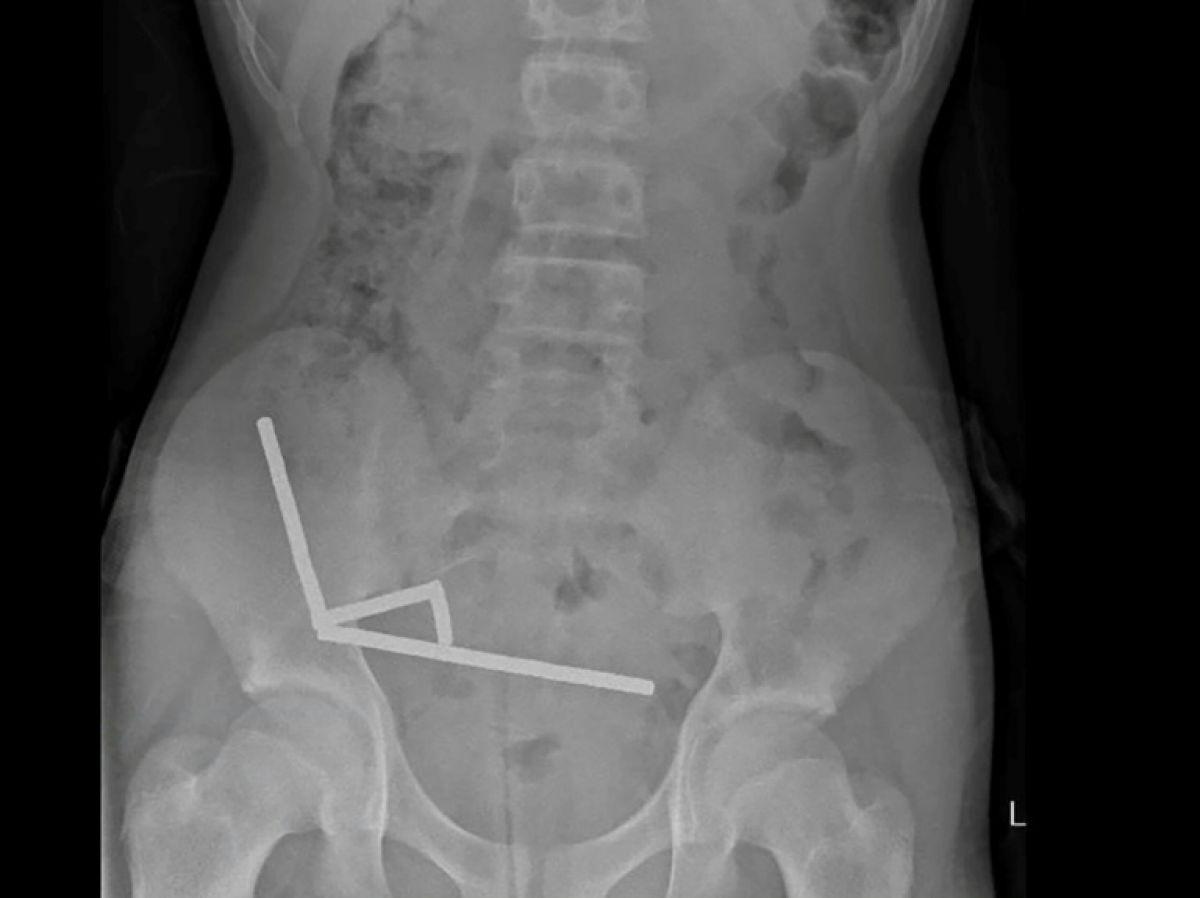

Africa-Press – Congo Kinshasa. Après avoir souffert de douleurs abdominales pendant quatre jours, l’adolescent a été transporté à l’hôpital de Tauranga, sur l’île du Nord. « Il a avoué avoir ingéré entre 80 et 100 aimants puissants au néodyme, de 5x2mm environ, une semaine plus tôt », indique un rapport des médecins de l’hôpital de cet hôpital, publié dans le New Zealand Medical Journal (NZMJ).

Ce type d’aimants, interdit en Nouvelle-Zélande depuis janvier 2013, aurait été acheté sur la plateforme chinoise d’e-commerce Temu. Les médecins ont déclaré que la pression exercée par les aimants avait provoqué une nécrose dans quatre zones de l’intestin grêle et du gros intestin du garçon.

Il a été opéré afin que l’on lui retire les aimants et les tissus nécrosés, et il a pu rentrer chez lui après huit jours à l’hôpital. L’article explique qu’une intervention chirurgicale à la suite de l’ingestion d’aimants peut entraîner des complications, telles qu’une obstruction intestinale, une hernie abdominale et des douleurs chroniques.